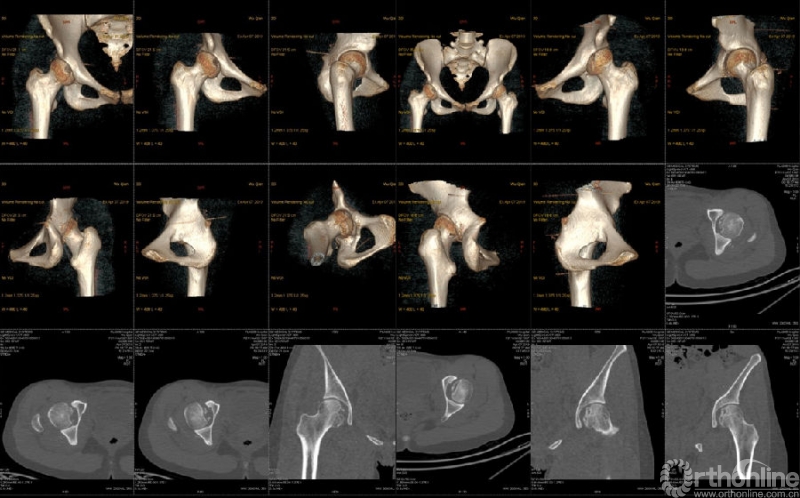

患者女,21岁,未婚。主诉车祸外伤致双髋部疼痛伴活动受限14小时入院。患者既往体健,无烟酒史及药物滥用史。

入院查体:生命体征平稳;双髋关节呈“弹性固定”位,即呈屈髋屈膝、内旋内收位,局部触痛明显,双髋关节活动障碍,双足动脉搏动可触及,双下肢末梢血运,各趾活动及触痛均正常。

骨盆CT示:双髋关节后脱位伴双股骨头骨折。

影像学检查